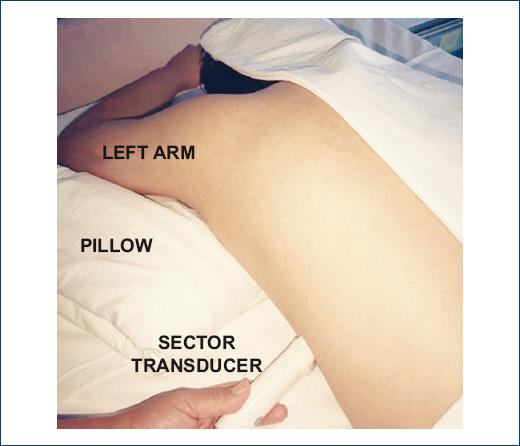

Subject’s PD positioning required for him/her to remain lying face down with the head turned to the side and the neck in neutral position; in addition, the left arm was positioned in the upward direction (toward the head) and a 10-cm-height pillow was placed in the ventral infraclavicular region, which allowed for a better image to be obtained (Fig. 2). The transducer was placed between the 4th and 5th left intercostal space toward the anterior axillary line. With this position, the aforementioned variables could be obtained in the PD position. This position is a modification of the swimmer position used in an intensive care unit in case transesophageal echocardiography is not available13.